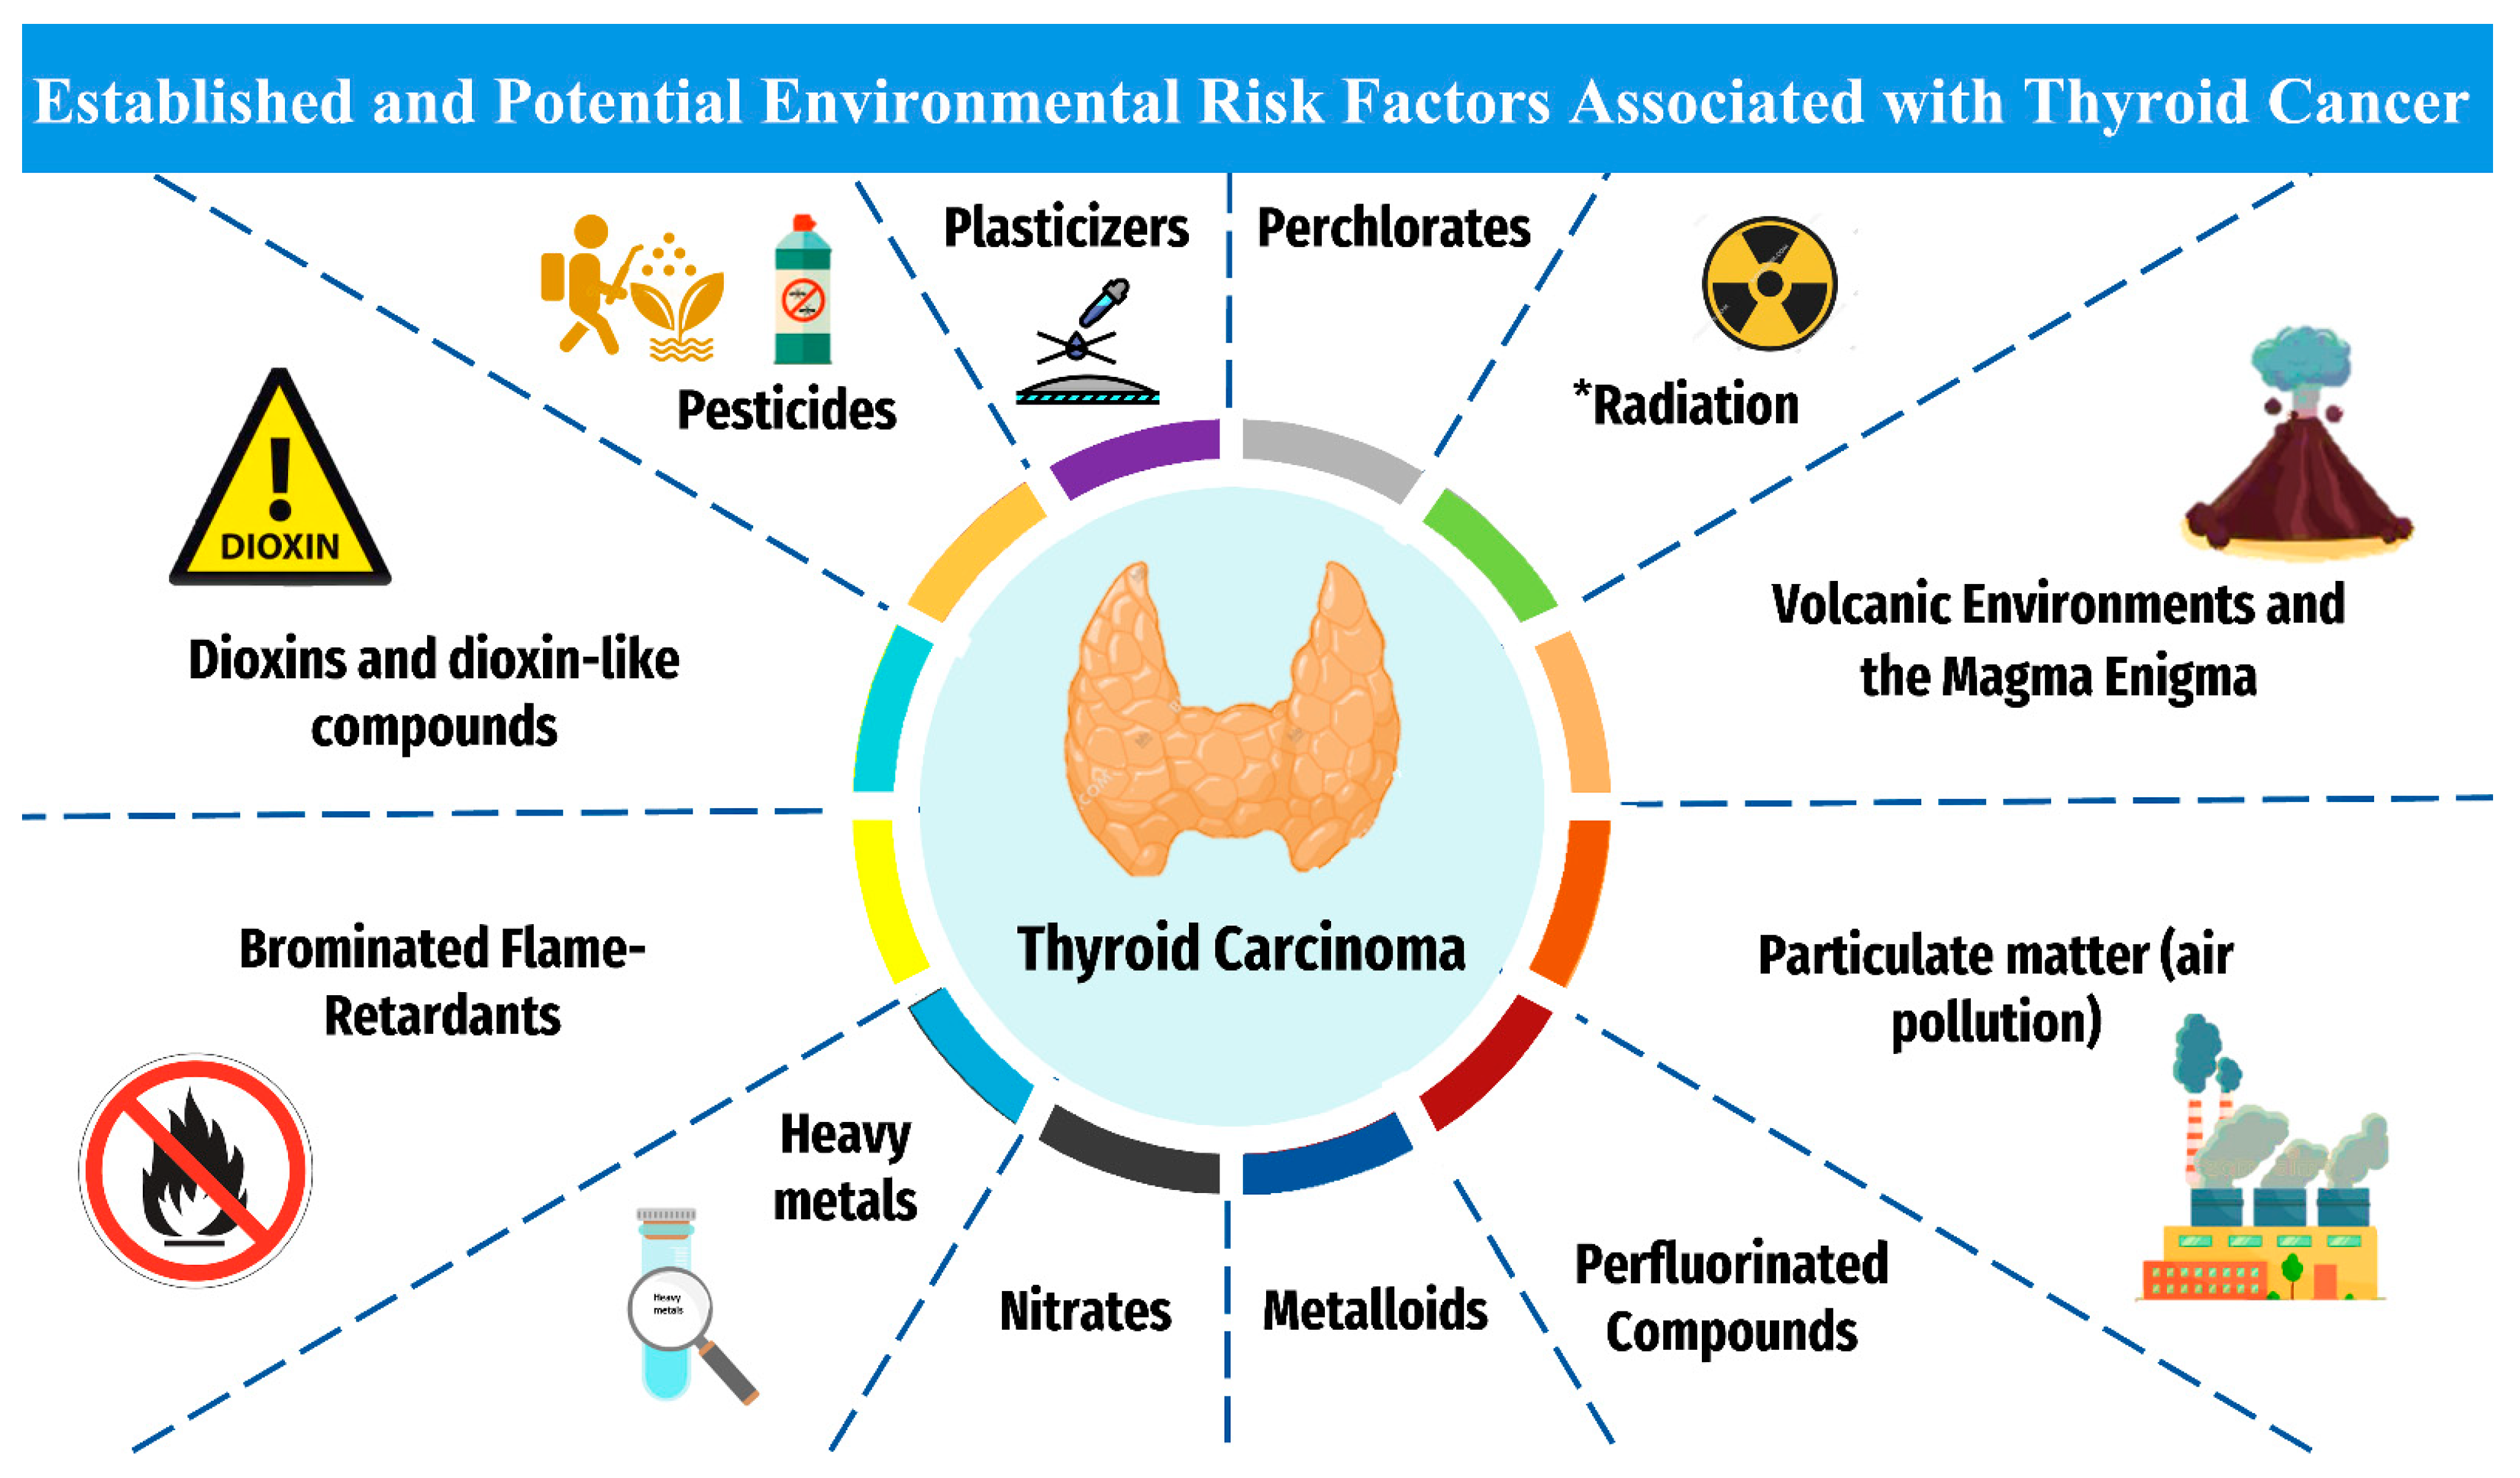

Cancers Free Full Text Thyroid Carcinoma A Review For 25 Years Of